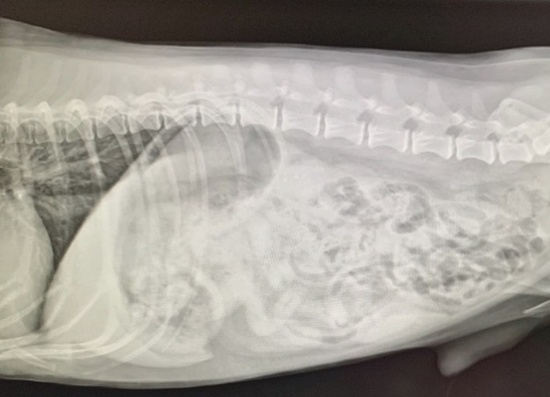

これが正常な犬の胸椎だとすると

下がアディルのです。椎骨が腰の方側(右側)は普通の形ですが、首側に向かって潰れたような形になってます。

もう、どうなっちゃってるの?というような形です。